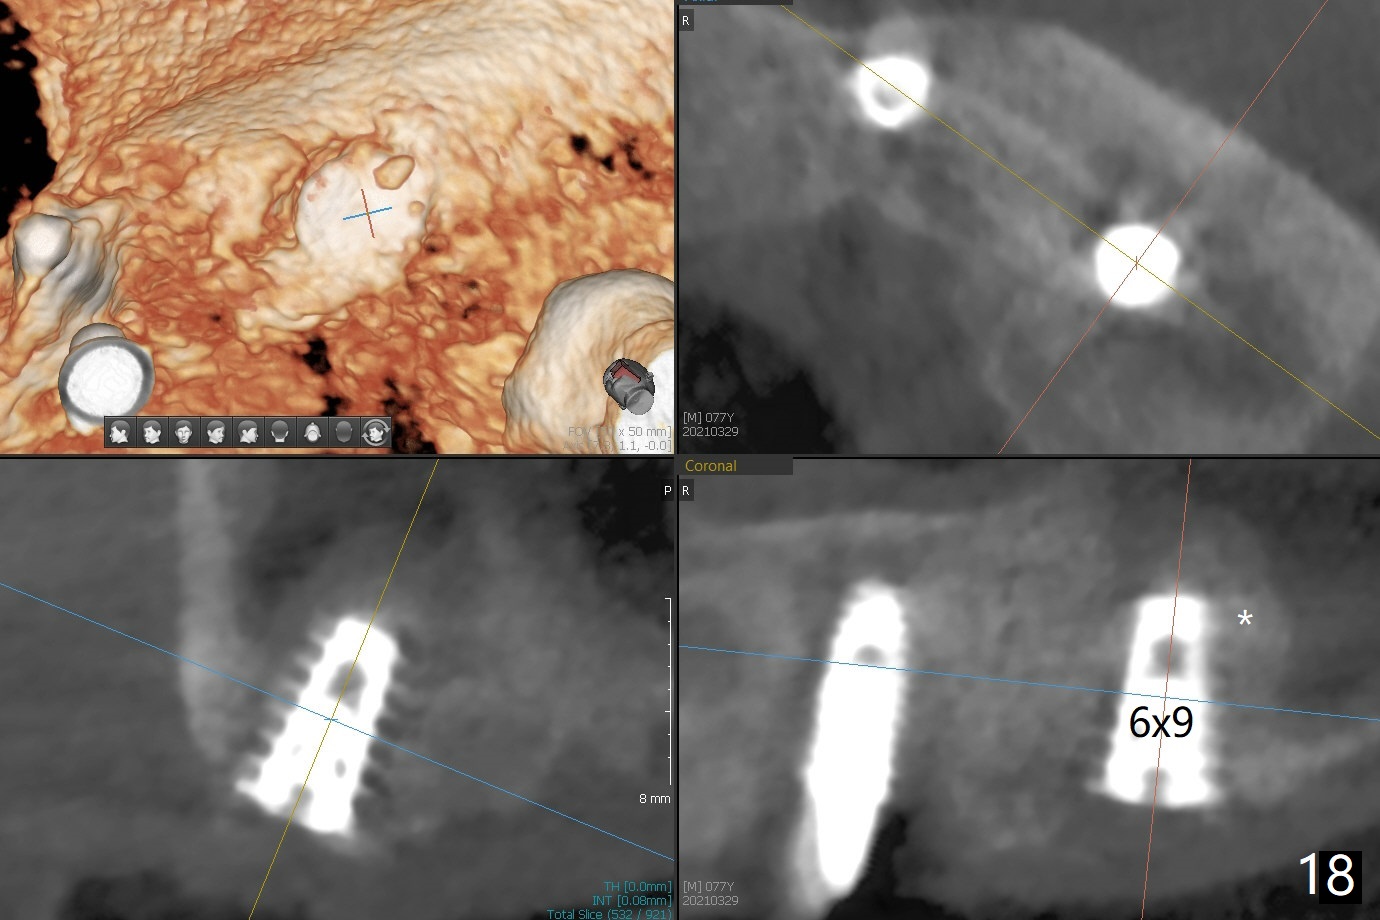

Osteotomy at #13 starts blindly (no incision or tissue punch) with bone expanders. After insertion of parallel pins, intraop CT shows that it is palatal with apparently buccal low bone density (Fig.1); the osteotomy for implant (Fig.2 green) should be shifted buccal and tilted mesial (red, parallel to #11) with incision. In contrast the position, trajectory and depth (Fig.3 <) of the initial osteotomy are acceptable at #11. The implant will be placed as it is (Fig.4). After taking a postop PA (Fig.5), the implant at #11 is placed a little deeper to make sure its slightly subcrestal placement (including distal incision at #11). Following placement of 3.5x4 and 3 mm ball abutments at #11 and 13, cortical allograft with PRF is placed around the implants, especially buccal (Fig.6,7 <). After suturing, the profile of the ball abutments is too low for RPD retention. Due to gravity other than bone density, the number of ball abutments for the maxilla should be more than for the mandible. Soft reline is done to the patient's satisfaction. The retention of the upper RPD after soft reline is satisfactory without pain 7 days postop (Fig.8). The implant at #13 is loose nearly 3 months postop (Fig.9 *: bone loss). The implant is removed while the ball abutment is untightened; the sinus floor is present. It appears that a longer and larger implant is necessary; a 4.5x10 mm dummy implant is unable to be seated deep or achieve primary stability (Fig.10). After sinus lift with 3 mm Bicon osteotome without bone graft, the dummy implant accomplishes the 2 tasks mentioned above (Fig.11). However there is no corresponding definitive implant in stock. Implant system needs to be changed; with a change in implant driver, the depth control is lost. The final implant is placed deep (Fig.12). With back up, stability is lessened; a healing screw is placed; with collagen plug, the wound is sutured (Fig.13). The wound heals 1 week postop (Fig.15). The RPD is soft relined. Retention from the ball abutment at #11 is apparently critical. The RPD and #11 implants (4 months postop) are stable, while the wound at #13 heals 1.5 months postop (Fig.15). There is space around the implant 5.5 months postop (Fig.16 *). The 5x10mm SM implant is found to be loose upon uncover and removed. After debridement, 5.3x8 mm SM and 5.5x9 mm IBS dummy implants are inserted without stability, while 6x9 mm definitive one with stability (Fig.17). Cortical allograft is placed in deficiency areas (*). The osteotomy has no roof (sinus floor), but the sinus membrane is intact. Small amount of bone graft (Fig.18 *) is placed before implantation. There appears to be bone around the new implant (Fig.19 (3D sagittal section) *).